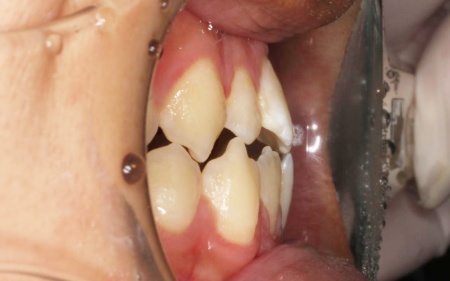

20代男性 受け口のように見える切端咬合をセラミックブラケットによる矯正治療で改善した症例

拝見したところ、上下前歯の先端同士が触れ合う「切端咬合(せったんこうごう)」の状態でした。

通常は上前歯が下前歯をわずかに覆うように重なりますが、患者様の場合は上下前歯の先端がほぼ同じ高さで噛み合っているため、受け口のような印象がみられました。

また、上下前歯の接触により下顎を前に出しにくく、後ろへ押し込まれやすい咬み合わせとなっています。

このまま放置すると、前歯の先端が少しずつすり減ったり欠けたりするリスクがあるだけでなく、顎の関節にも負担がかかり、食べ物を噛む機能や発音に影響が出るおそれもあります。